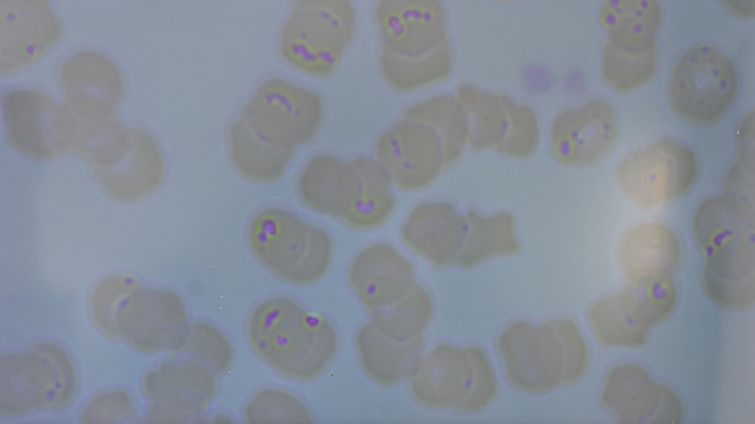

獣医は相変わらずの塩対応だったが、顕微鏡の画像と採血結果、資料を見せてくれた。

マイコプラズマ感染症。死亡率は30%。猫ではオスに好発。